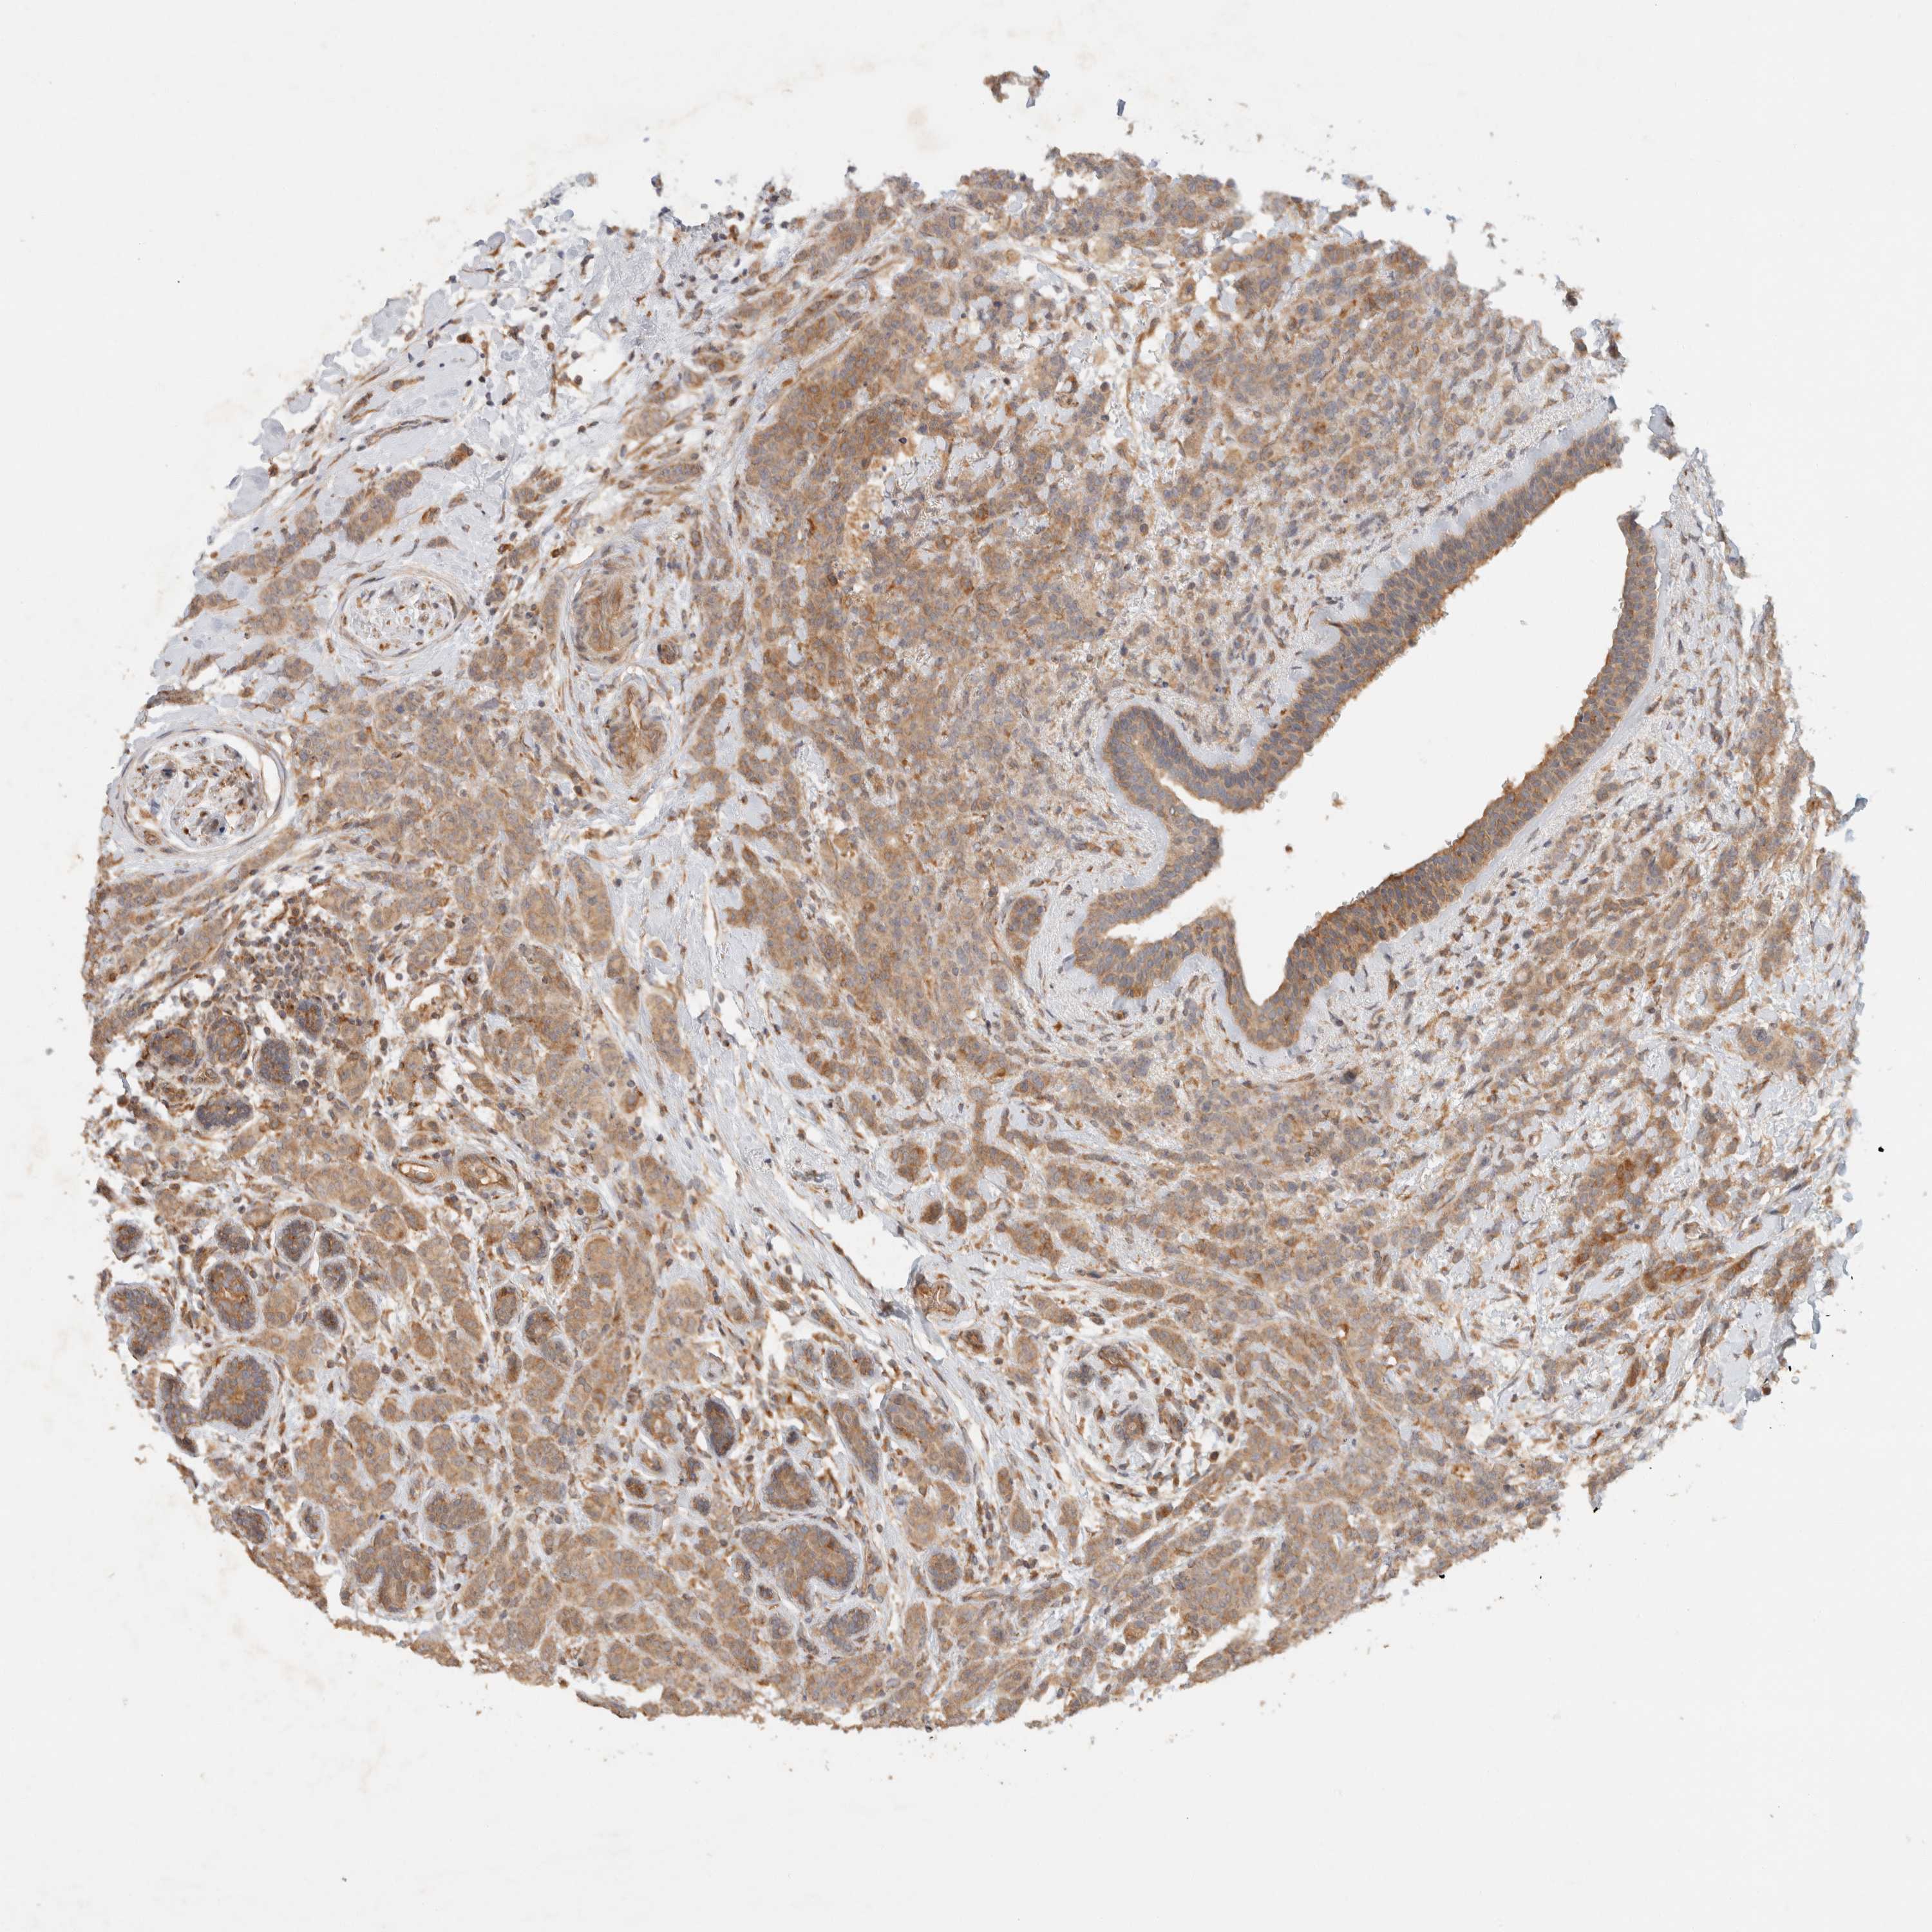

CANCER BREAST CANCER Show tissue menu

BRCA TCGA BRCA VALIDATION PROTEIN EXPRESSION

ANTIBODIES

AND

VALIDATION